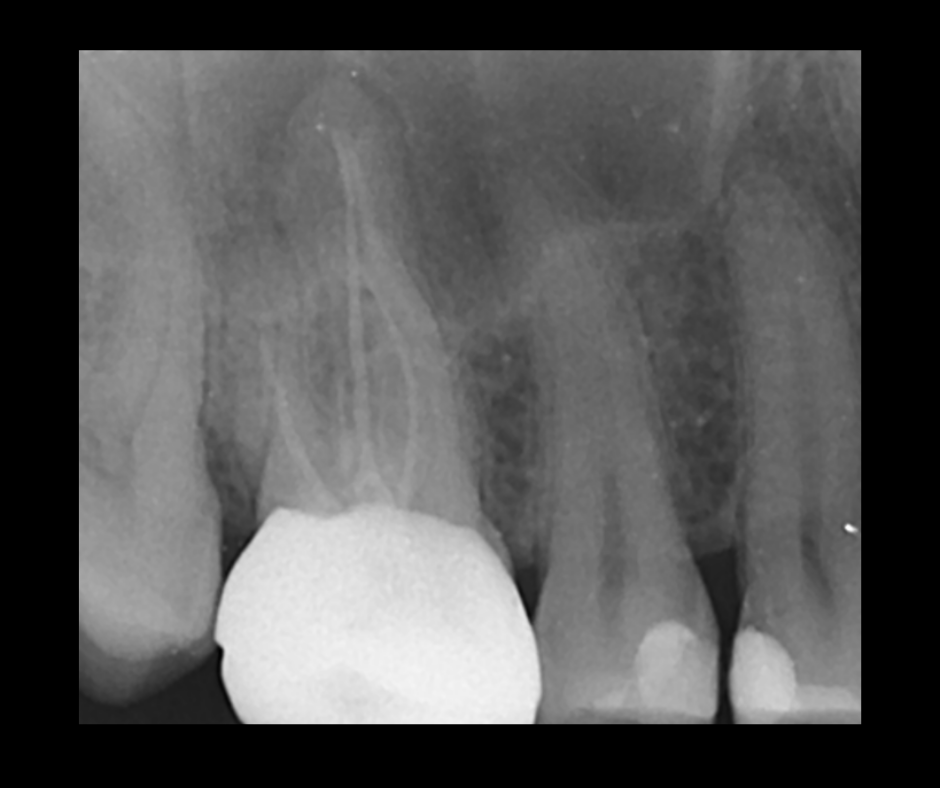

This course focuses on modern single-file endodontic systems, guiding participants through diagnosis, case assessment, access cavity design, canal location, root canal system preparation, and obturation techniques.

• To re-examine access cavity design and its importance in endodontic success

• To understand the importance of achieving patency and mechanical glidepath with hand & NiTi instruments

• To gain confidence in mechanical preparation using rotary and reciprocating NiTi shaping instruments

• To acknowledge the updates in endodontic irrigation and methods of improving irrigation efficacy within the root canal system

• To gain confidence in endodontic obturation and develop an understanding of various obturation techniques and methods of developing predictable, reproducible endodontic obturation